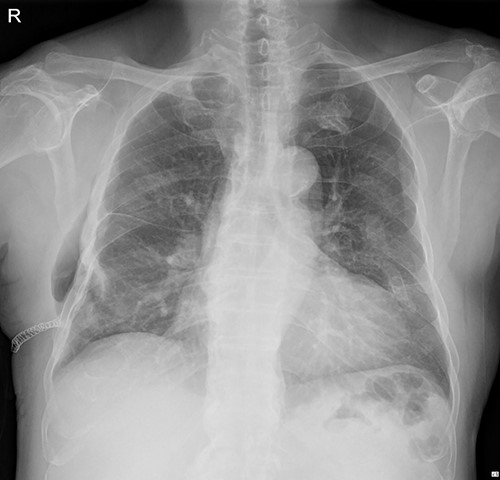

The patient underwent plate removal surgery on 24 February 2022. The operation was performed routinely. Under general anesthesia, a small incision was made on the previous operation scar. After sufficiently dissecting surrounding tissues and muscles, we skimmed implants off the rib cage. Then, a seven-French sizes (FR) drainage catheter was placed below the serratus anterior muscle (SAM) to manage potential minor complications. Because we usually do not invade the rib cage during plate removal operations, there was no need to be concerned about lung injury. The patient was discharged on hospital Day 2 with the submuscular drainage catheter removed (Fig. 2.).

Immediate postoperative chest X-ray after plates removal (24 February 2022).